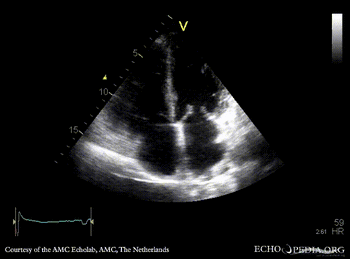

A4CH: normal systolic function of left ventricle A2CH